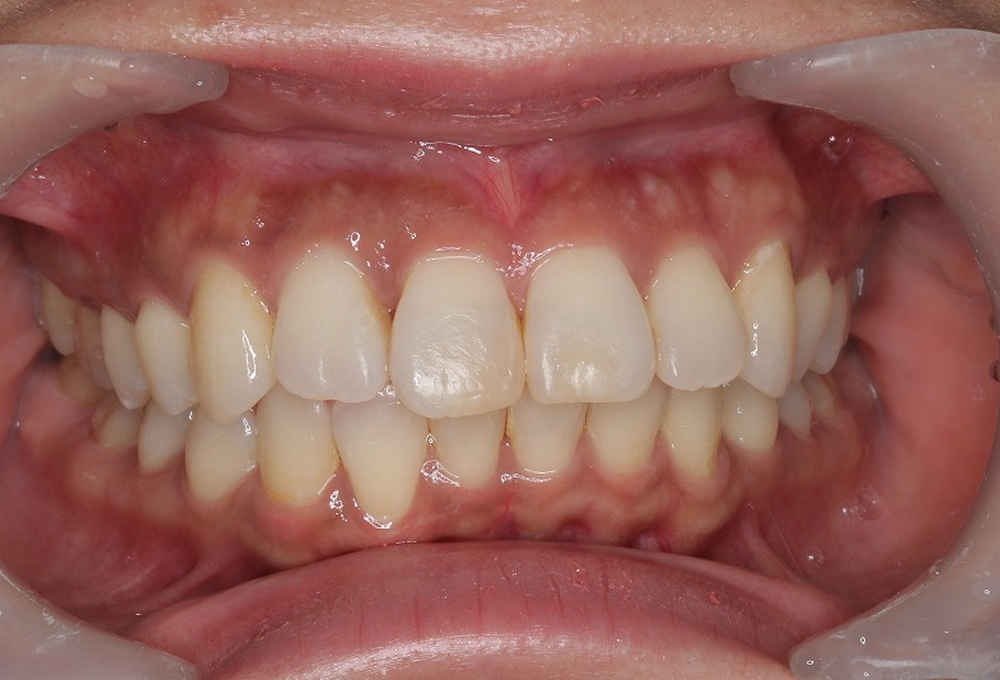

⑤拡大床後、6前歯のみ約3ヶ月ブラケットを装着し矯正

⑥ブラケットをはずし矯正終了。綺麗な歯並びになりました